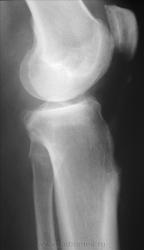

Или остеоид-остеома. Сделайте КТ

Тогда порекомендуйте аспириновый тест.